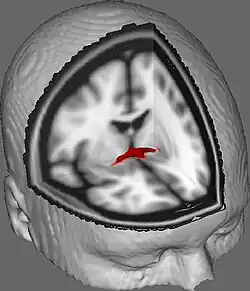

![]() Sección coronal del encéfalo a través de la comisura anterior. (Etiqueta de la comisura anterior a la izquierda, tercera desde abajo) | ||

La comisura anterior (también conocida como la precomisura) es un haz de fibras nerviosas que conecta los dos lóbulos temporales de los hemisferios cerebrales a través del línea media. Se encuentra frontal a las columnas del fórnix.

En secciones sagitales la comisura anterior tiene una forma oval con un largo eje vertical de unos 5 milímetros.